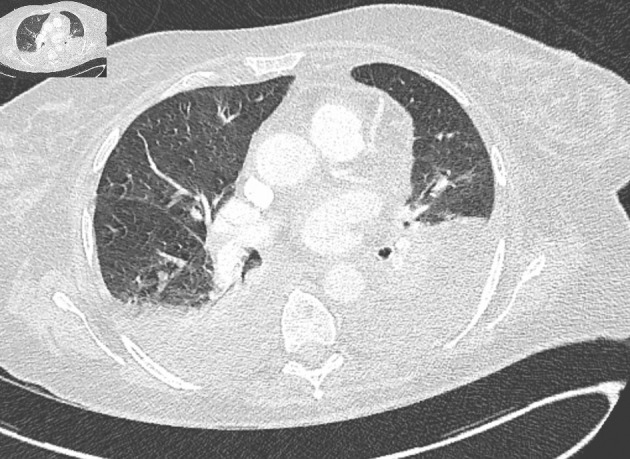

Immunotherapy is a rapidly expanding cancer treatment strategy. Dostarlimab is administered as the first-line treatment for metastatic endometrial cancer in combination with chemotherapy. Herein, we describe the case of a 72-year-old female patient who developed hemophagocytic lymphohistiocytosis after receiving a single dose of 500 mg of dostarlimab. The patient's clinical outcome improved after treatment with ruxolitinib and corticosteroids. Oncological treatment was resumed in combination with chemotherapy alone.